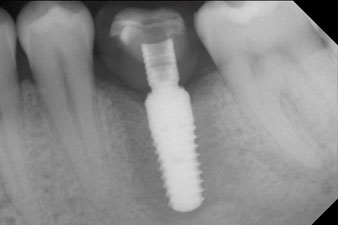

Die Abschlussbilder zeigen die verschraubte monolithische Kompositkrone in situ und die Röntgenkontrolle (Abb. 9 und 10) (6).